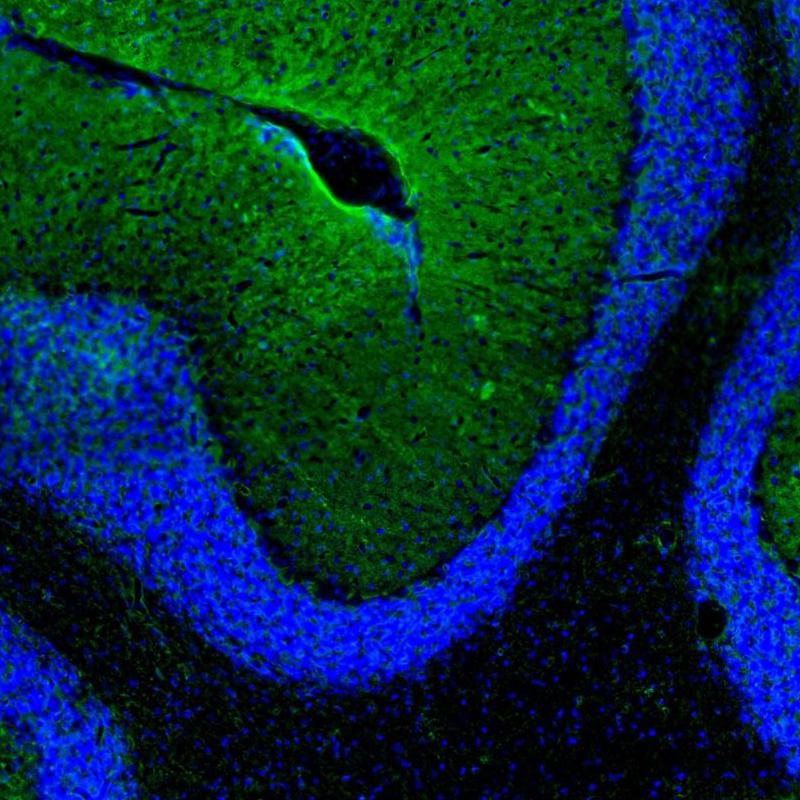

Immunohistochemistry analysis in human cerebral cortex and liver tissues using HPA014784 antibody. Corresponding AQP4 RNA-seq data are presented for the same tissues.

The Anti-AQP4 antibody (HPA014784) specifically targets Aquaporin 4 (AQP4), a vital water channel protein primarily expressed in the brain and spinal cord. AQP4 plays a crucial role in maintaining water homeostasis and is significant in various physiological and pathological processes.